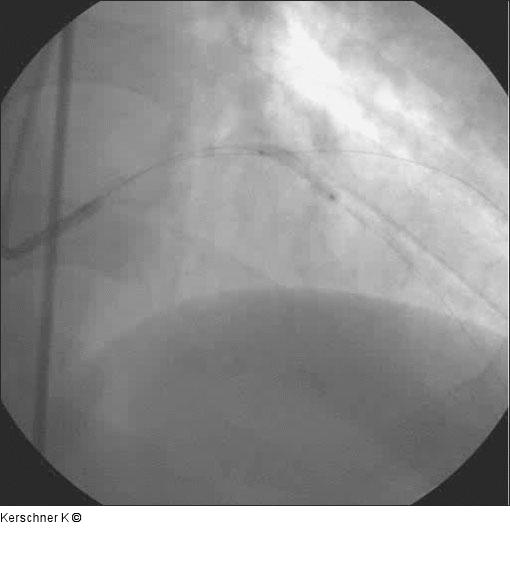

Abbildung 4: Vordilatation LAD Vordilatation LAD mit 2,5/20-mm-Ballon - 16 atm. |

Vordilatation LAD mit 2,5/20-mm-Ballon - 16 atm. |